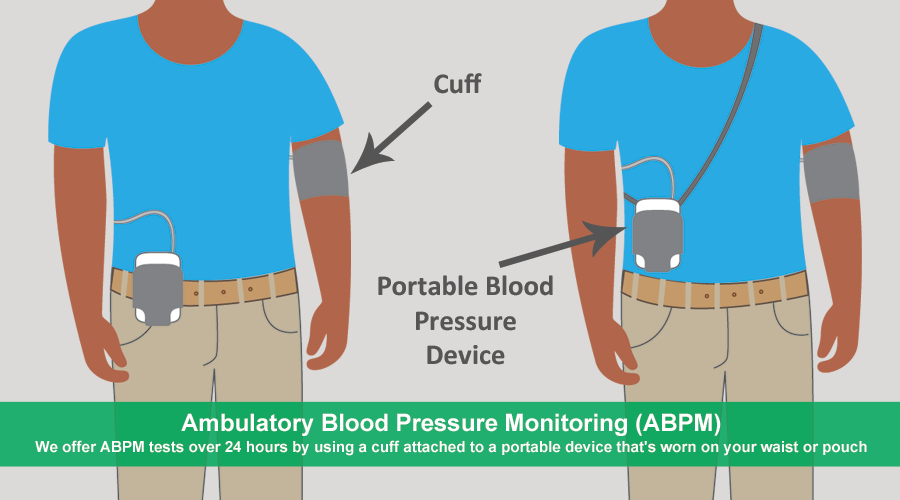

We offer a wide range of products and services, some of which include Dispensing both NHS and Private Prescriptions, Repeat Dispensing, New Medicine Service, FREE Prescription Collection and Delivery Service in the local area, Self-Care Medicines Scheme, Pharmacy First Service, Weight Loss Treatment, Stop Smoking Service, Travel Vaccinations and General Immunisation, Flu Vaccination, Covid-19 Vaccination, Blood Pressure Monitoring, Emergency Hormonal Contraception, Erectile dysfunction, as well as Ear and Nose Piercing services just to name a few.